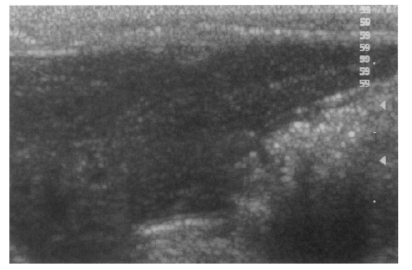

Histopathological findings

Microscopically, hematoxylin-eosin stained sections of the resected extrahepatic bile ducts showed the features of active and chronic clonorchiasis, i.e., mucosal hyperplasia of the extrahepatic bile duct, ductal wall thickening, slight periductal fibrosis and periductal inflammation in the primary and secondary infection control groups, and the infection following immunization group (Fig. 10). Worms were found in the bile ducts of all rats (Fig. 10), and obvious desquamation of the duct epithelium was observed in two rats. In the reinfection groups, mucosal hyperplasia of the extrahepatic bile duct, ductal wall thickening, and slight periductal fibrosis were noted; however, periductal inflammation was considerably milder than that in the other groups. In these groups, no significant difference was observed between rats reinfected at 6 and at 26 weeks.

Fig. 10

Histopathological photograph of a rat in the primary infection control group 4 weeks after C. sinensis infection, showing some adult worms (arrowheads) in the bile duct associated with papillary and adenomatous hyperplasia of bile duct mucosa, ductal wall thickening, minimal periductal fibrosis, and periductal inflammation (arrows).